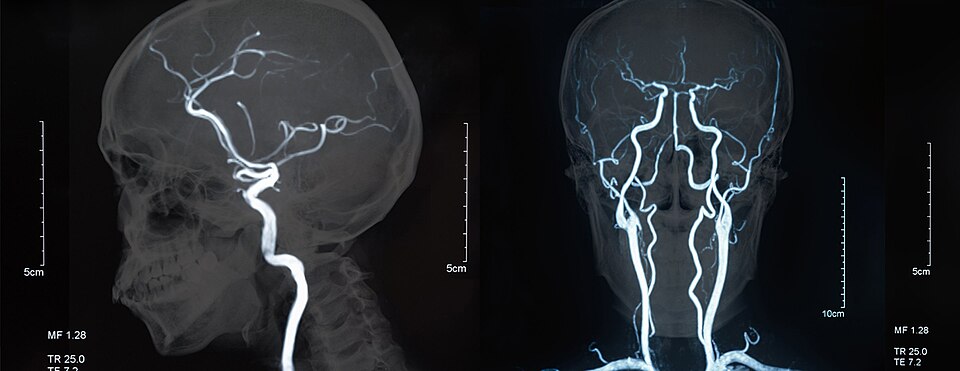

Magnetic Resonance Angiography (MRA) is a type of MRI scan used to visualise blood vessels and detect various vascular conditions by employing time-of-flight (TOF) and contrast-enhanced (CE) techniques. TOF-MRA is helpful for imaging arteries and veins without contrast agents, while CE-MRA uses gadolinium-based agents to enhance blood vessel visibility, providing high-resolution images quickly. MRA is used to diagnose conditions such as peripheral artery disease, renal artery stenosis, and arterial dissection, as well as to identify blood flow abnormalities, narrowing or blockages, and aneurysms.